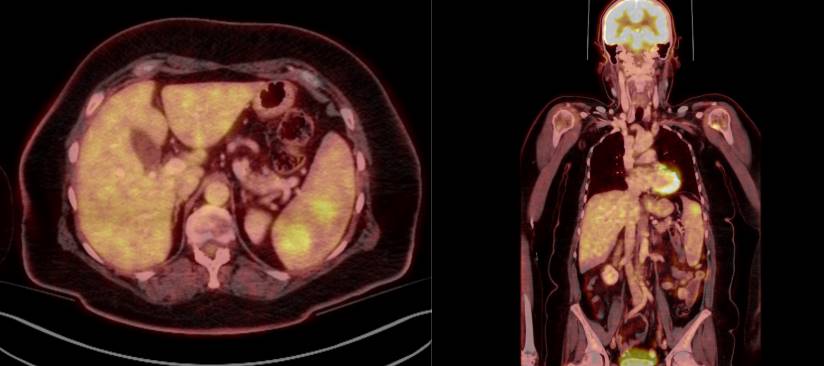

More than 2 years later, new multiple hypodense splenic nodules appeared, with the largest measuring up to 2.5 cm, along with a subtle contour protrusion at the cranial-dorsal pole. FDG-PET/CT demonstrated hypermetabolic splenic lesions and suspicious foci in the left humeral head and lumbar vertebra L4 (Figure 1). A bone marrow biopsy at L4 showed increased myelopoiesis and aberrant lymphoid aggregates with B-cell predominance, but definitive classification was not possible.

Figure 1. FDG-PET/CT showing hypermetabolic lesions in the spleen.